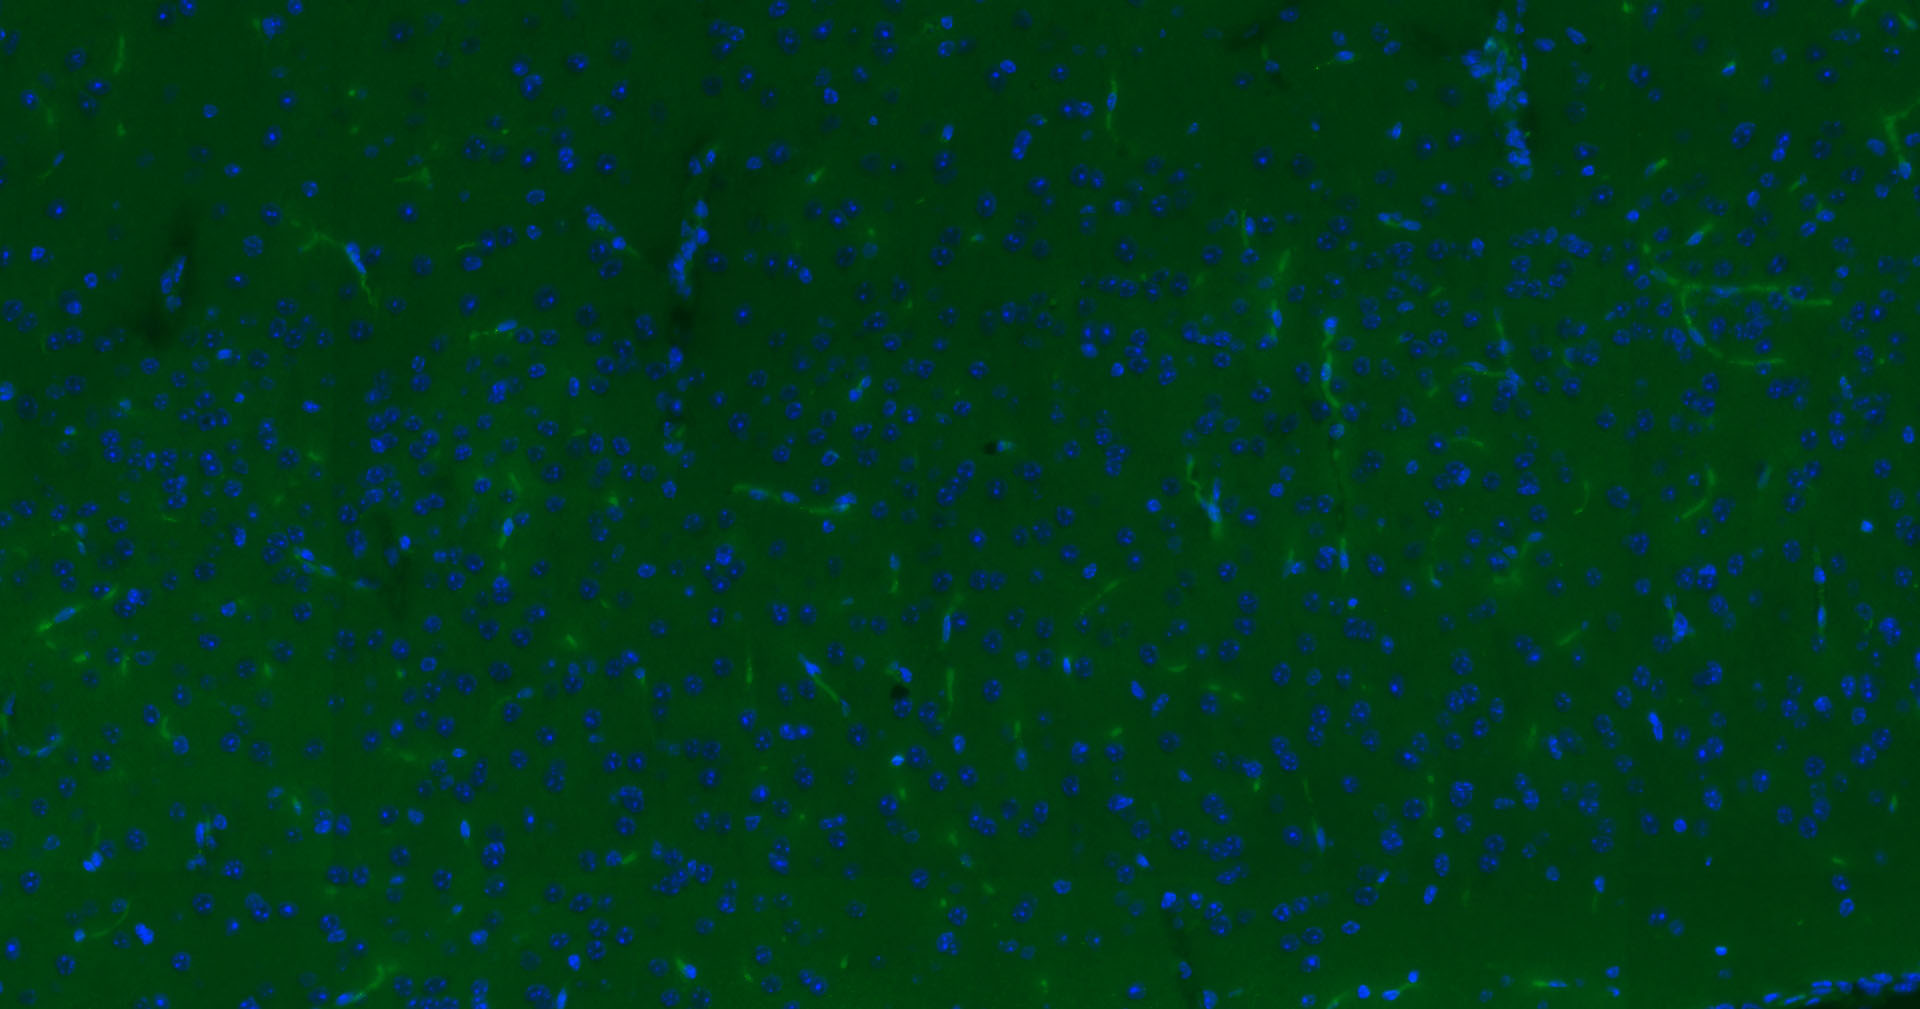

Paraformaldehyde-fixed, paraffin embedded Mouse Cerebrum; Antigen retrieval by boiling in sodium citrate buffer (pH6.0) for 15 min; Antibody incubation with CD34 Polyclonal Antibody, Unconjugated (bsm-54470R) at 1:100 overnight at 4°C. Followed by conjugated Goat Anti-Rabbit IgG antibody (green, bs-0295G-BF488), DAPI (blue, C02-04002) was used to stain the cell nuclei.